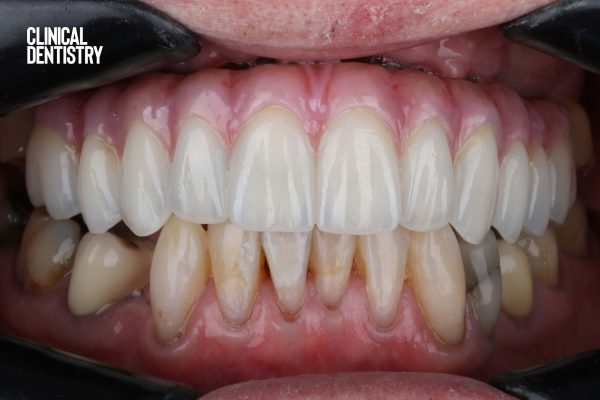

Digitally planned, immediate upper full-arch implant-supported restoration: case study

Usman Riaz reports on an immediate implant plan for a new dental referral patient with failing heavily restored dentition A…

Clinical Dentistry